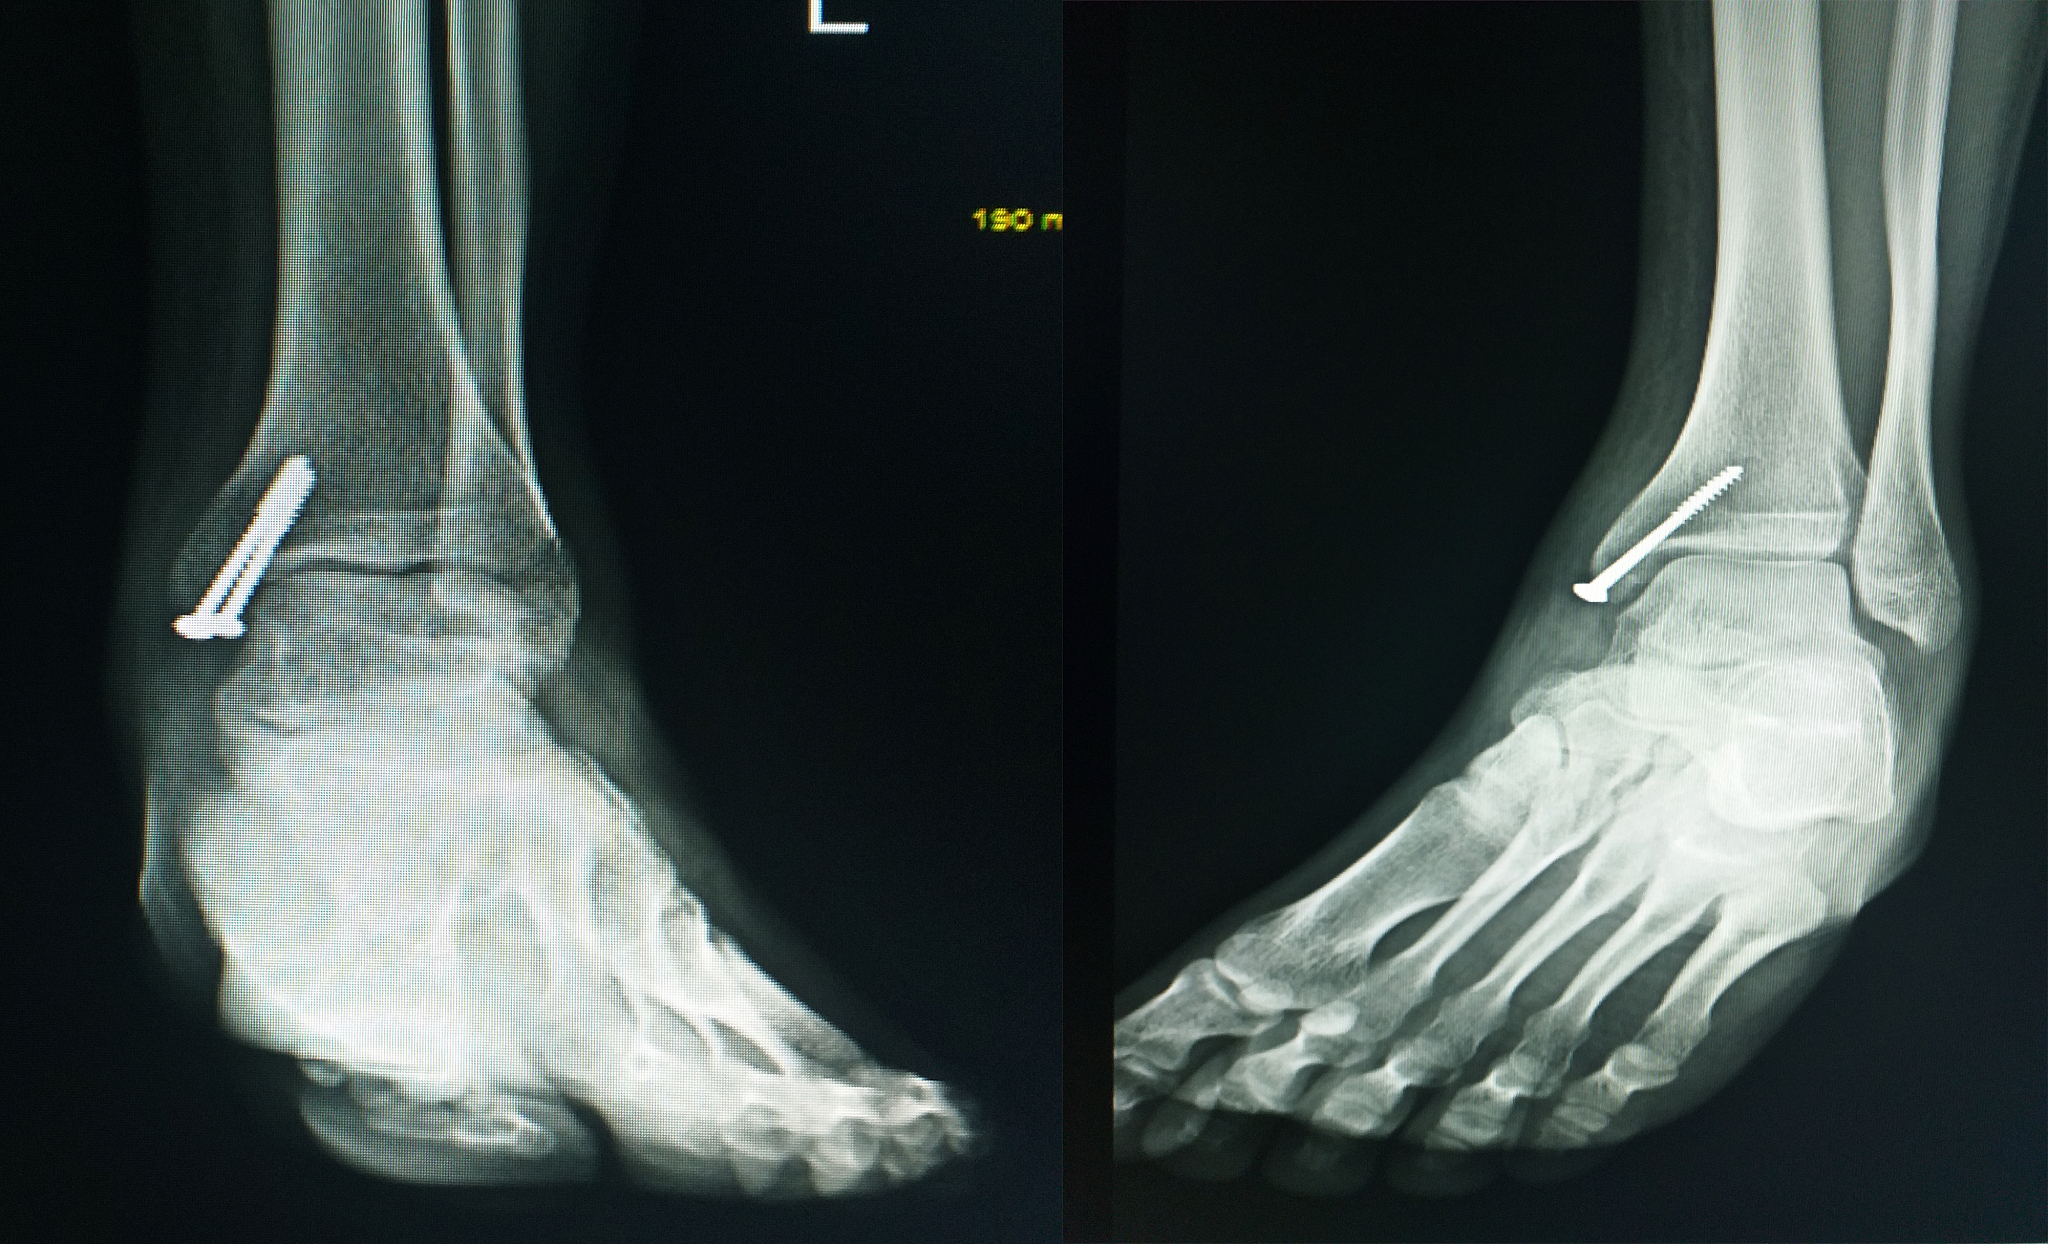

4. 关节固定:在韧带修复或重建完成后,医生可能会使用金属螺钉、钢板或其他固定材料来稳定踝关节。